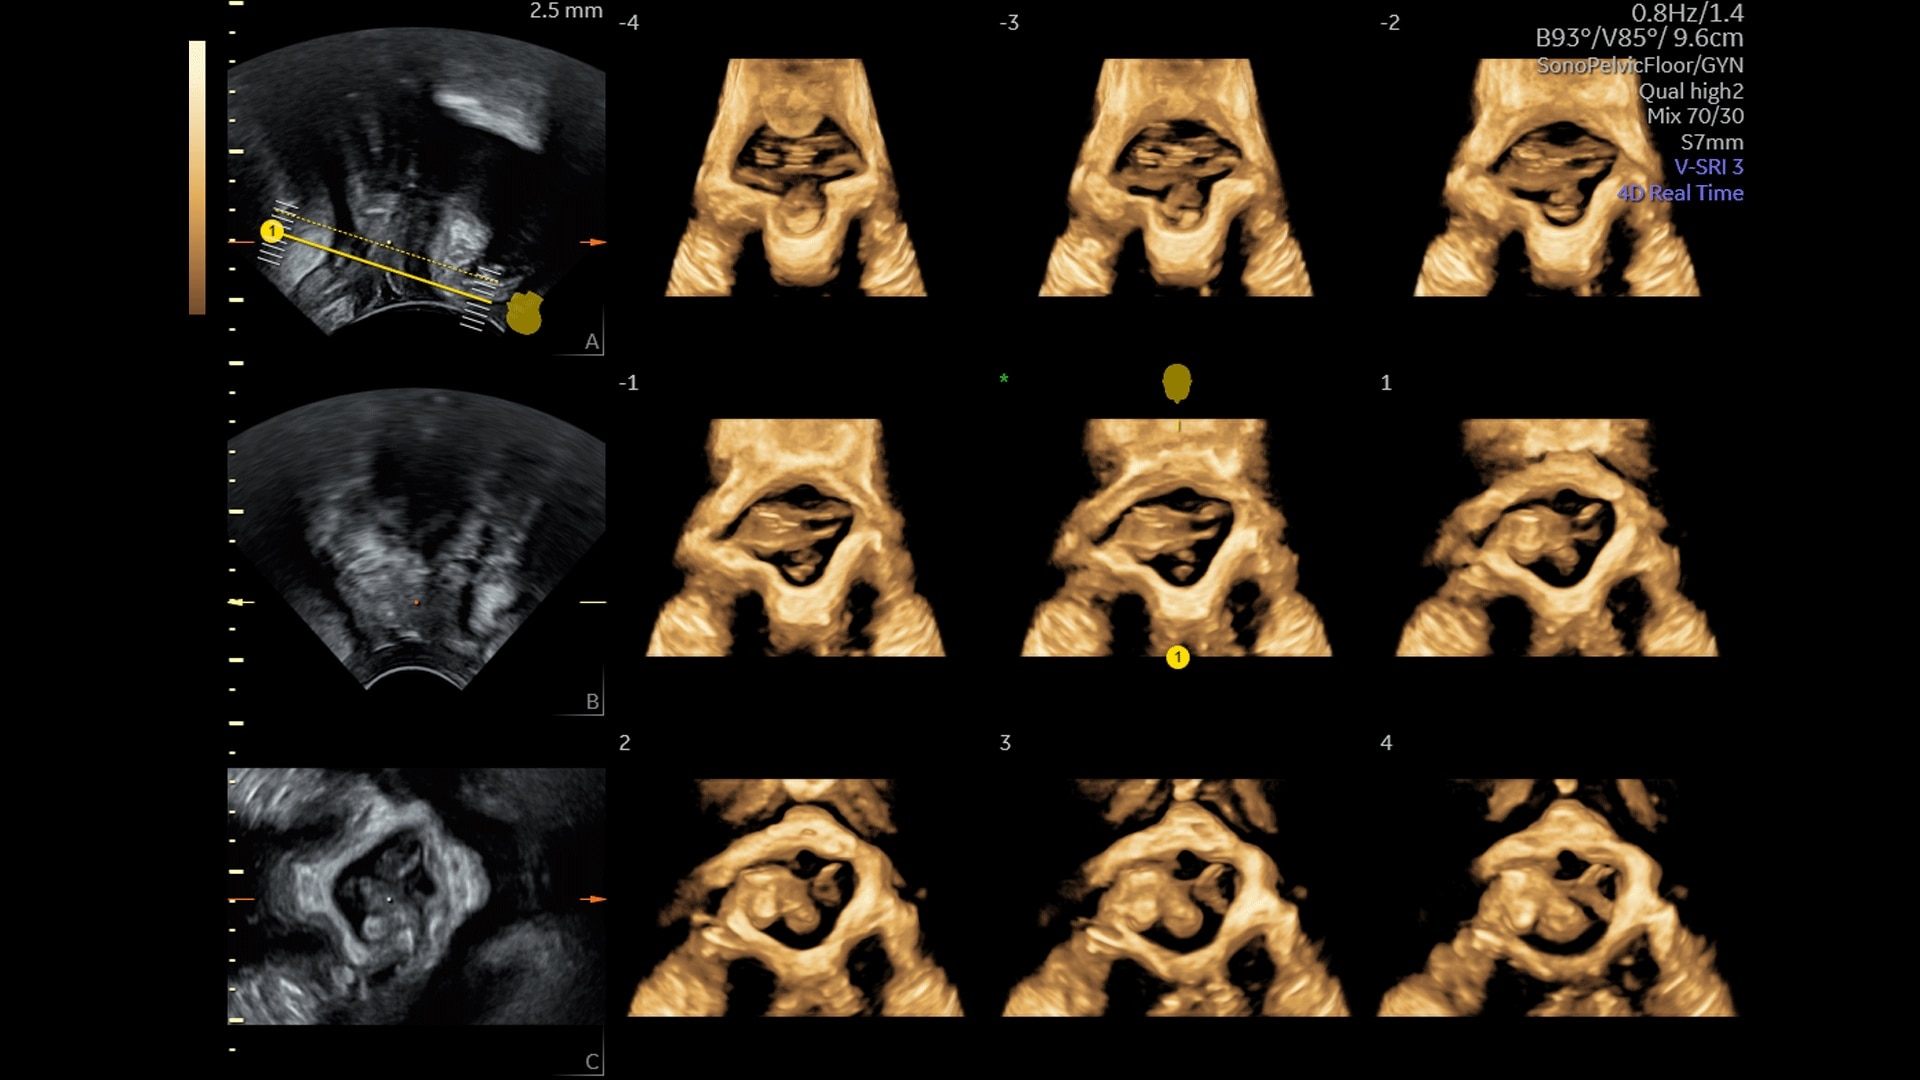

Generate spectacular 2D/3D and color Doppler images with increased penetration and stunning clarity, to help visualize critical details needed for diagnostic assurance. The Lyric Architecture unlocks new imaging and processing power to expand your imaging capabilities for years to come

Experience a new level of efficiency with the highly intuitive and customizable ultrasound that promotes progress and productivity. Leverage the power of artificial intelligence and easy-to-use automation tools that streamline workflows and make a real impact every day.